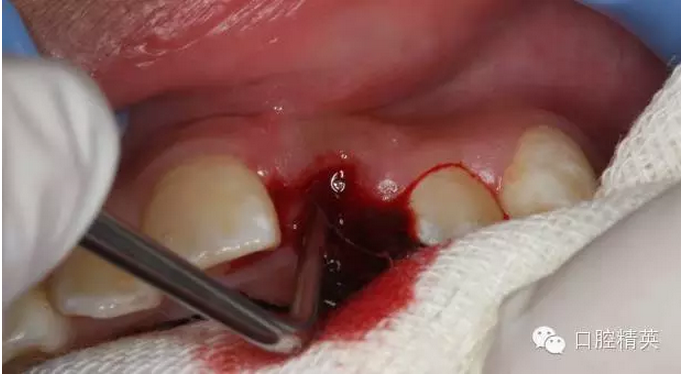

圖13.清理21牙槽窩

圖14.再植21離體牙